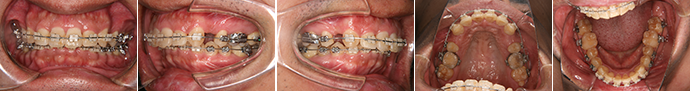

| 主訴 | 噛み合わせが逆、八重歯 |

| 年齢・性別 | 20歳 / 女性 |

| 治療方針 | オトガイの突出感が強く、前歯だけでなく臼歯部も反対咬合。低位舌が認められる。顔貌改善には外科矯正の方がベストだが本人が希望しなかったため、MFTを行ったのち上顎拡大、上下マルチブラケット装置のみで治療を行った。左上中切歯に打撲の既往あり。 |

| 抜歯部位 | 上下顎左右第3大臼歯(計4本) |

| 使用装置 | クウォードヘリックス、マルチブラケット装置 |

| 治療期間 | 25か月 |

| リテーナー | 上顎インビジブル、下顎スプリングリテーナー |

| 費用 | 825,000円(税別) |